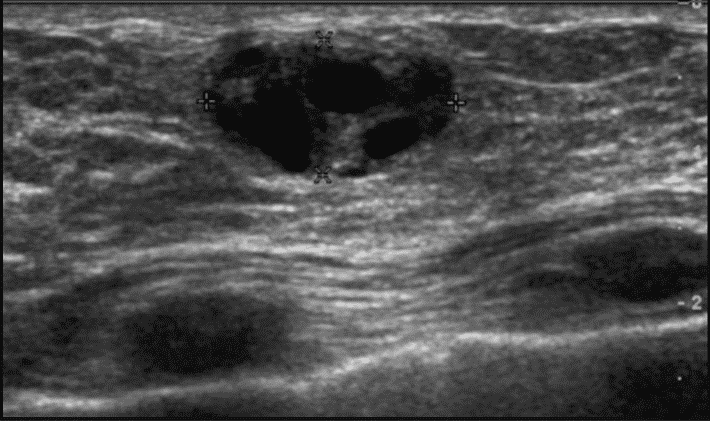

Заподозрить наличие патологии врач может уже при простом визуальном осмотре и пальпации. Для подтверждения диагноза применяются аппаратные способы исследования:

- УЗИ (ультразвуковое исследование). С его помощью можно точно определить размер и местоположение серомы. Применяется для диагностики осложнения на ранних стадиях.